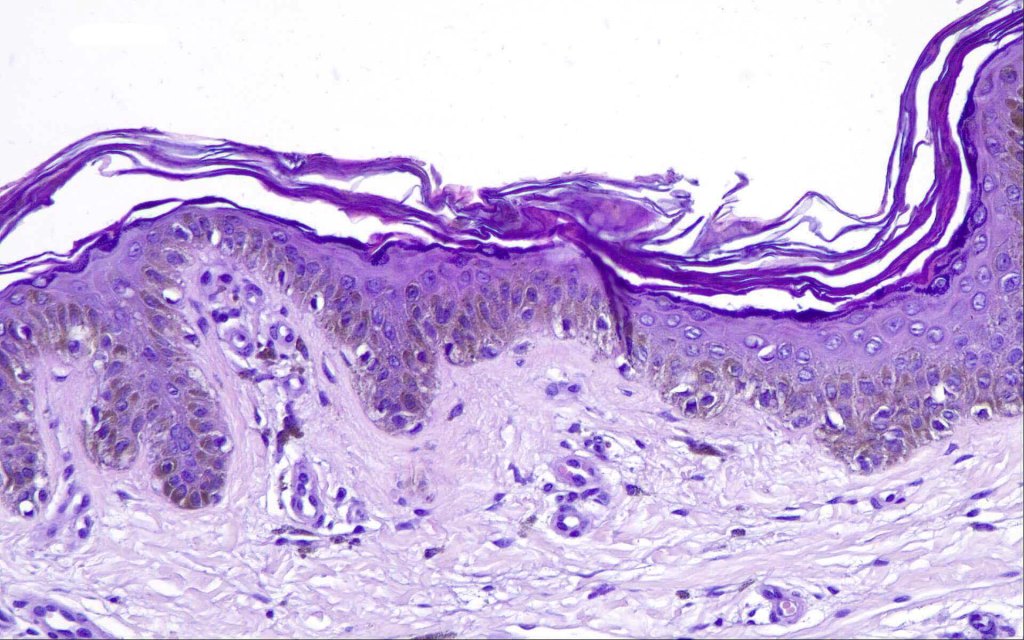

- A broad lentiginous proliferation of atypical melanocytes unasscoiated with any loss of the rete ridges

3. The cells can be present singly, in short pallisades or can extend along a large section of epidermis

4. Pagetoid spread is sometimes seen in more established lesions

7. Fibroplasia not seen and elastosis is either mild or absent